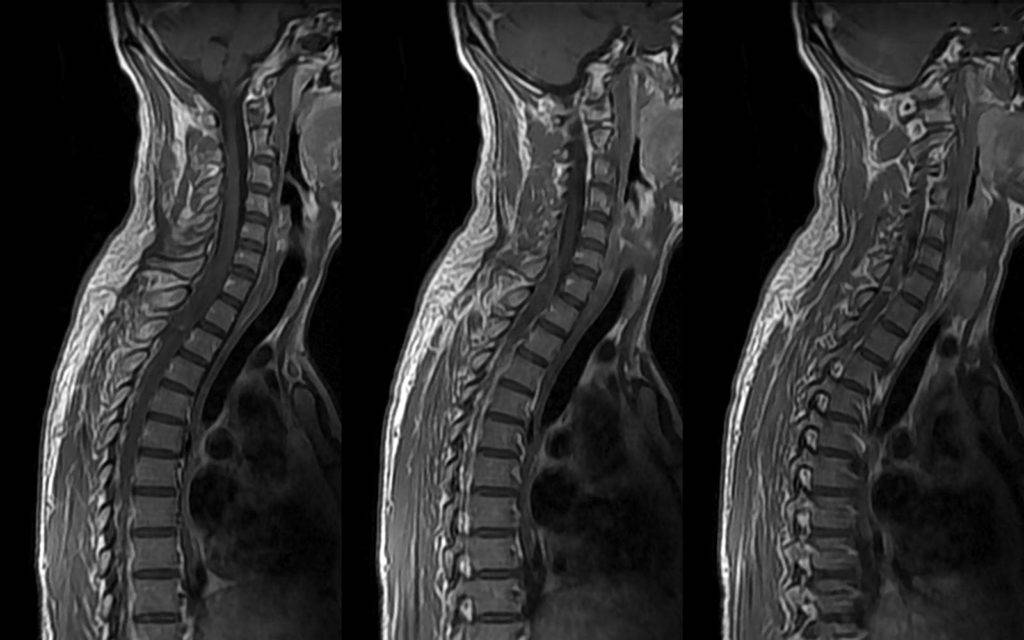

Вторичные опухоли в позвоночнике

Если рак пустил вторичные опухоли в позвоночник, то это прямая угроза для жизни человека. Это объясняется множественным размножением очагов в этой области. Если в позвоночнике вторичные опухоли выявлены несвоевременно, то прогноз будет неутешительным. Больному осталось жить всего лишь несколько месяцев.

Именно поэтому, если пациент знает, что у него рак и у него появляется болезненность в области позвоночника, которое усиливается ночью, то ему необходимо в обязательном порядке обратиться в медицинский центр для прохождения обследования. О появлении гнойников в позвоночнике также свидетельствуют нарушения невралгического характера.

Если не проводить лечение гнойников в позвоночнике, то у больного могут онеметь конечности. Также вторичные опухоли приводят к нарушению нормальной работоспособности внутренних органов, что приводит к летальному исходу больного. Для того чтобы максимально точно сделать прогноз, необходимо провести диагностику. Она позволит определить степень развития рака, а также узнать о длительности жизни человека с воспалительными очагами в позвоночнике.